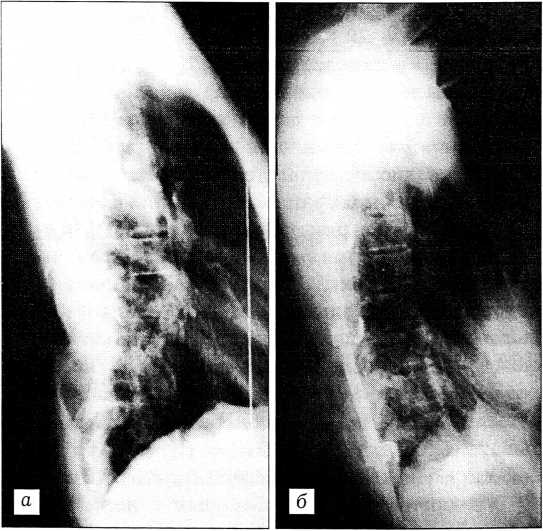

Грудной кифоз менее 20° был выявлен у 8 больных — в среднем 8,1° (6-14°). После вмешательства у этих пациентов отмечено увеличение грудного кифоза в среднем до 22,5° (14- 29°) (рис. 2).

Рис. 2. Та же больная. а — до операции: грудной лордоз 11°; б — после операции: сформирован грудной кифоз 14° (через 6 мес — 15°).